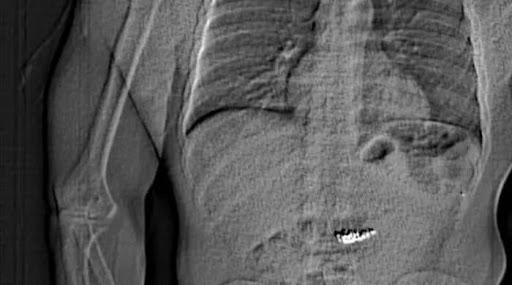

A man allegedly swallowed stolen earrings costing more than half a million dollars just moments before he was taken into custody by Florida...